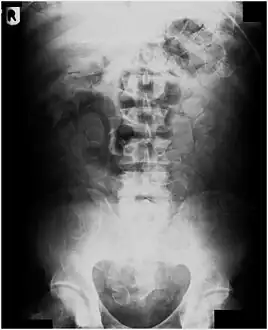

If the person who swallowed the foreign body is doing well, usually an x-ray image will be taken which will show any metal objects, and this will be repeated a few days later to confirm that the object has passed all the way through the digestive system. Also it needs to be confirmed that the object is not stuck in the airways, in the bronchial tree.

- Abdominal X-ray showing small packages of cocaine swallowed by a trafficker.

- Vibrator stuck in the rectum can be seen on this abdominal X-ray.